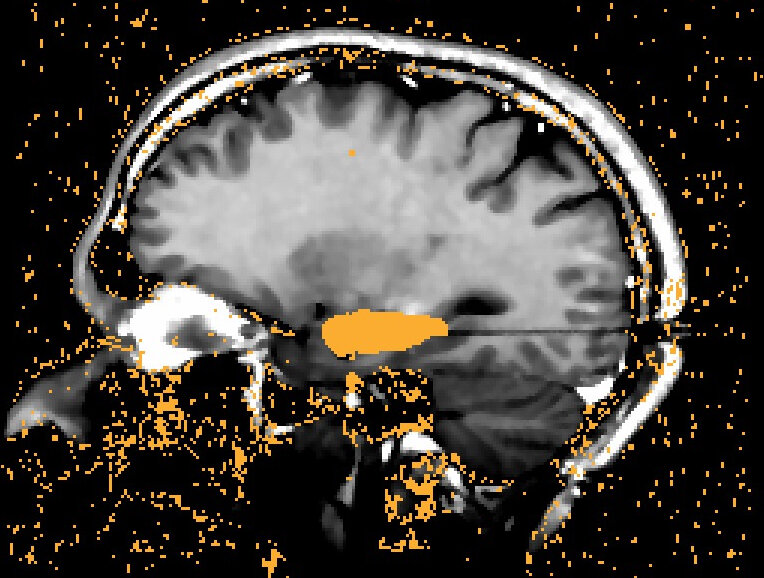

Laser interstitial thermal therapy (LITT) used to treat medial temporal sclerosis causing temporal lobe epilepsy

What a laser ablation lesion looks like on an MRI after the procedure